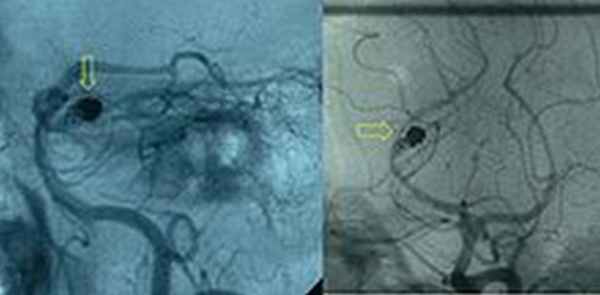

После верификации диагноза субарахноидального кровоизлияния, необходимо выявить его источник. При подозрении на разрыв артериальной аневризмы, необходима её визуализация методом ангиографии сосудов головного мозга (который позволяет осуществить одновременное эндоваскулярное хирургическое вмешательство) или КТ-ангиографии.![Артериограмма, демонстрирующая эндоваскулярно облитерированную аневризму (обозначена желтой стрелкой) задней мозговой артерии с остаточным аневризматическим мешком]()

Рис.Артериограмма, демонстрирующая эндоваскулярно облитерированную аневризму (обозначена желтой стрелкой) задней мозговой артерии с остаточным аневризматическим мешком.Профилактика САК: проведение МРТ, МРА при развитии упорных головных болей пульсирующего характера, сопровождающихся различной неврологической симптоматикой, эпилептических припадков с целью раннего выявления сосудистых мальформаций1головного мозга.